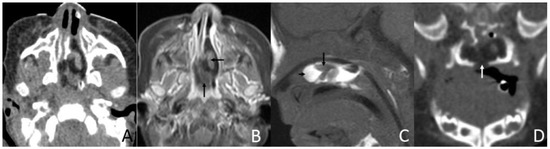

Figure 5. CT of a 1-month and 6-day girl presenting shortly after birth due to being unable to suck and having a mandibular mass. (A,B) Coronal and sagittal CT, displayed in the soft-tissue window, show the irregular fat (short arrow) and soft tissue (long arrow) density mass originating from the back side of the left soft palate. (C) Sagittal CT, displayed in the bone window, shows that there were multiple irregular dense shadows (long arrow) above the mass that were not seen, were excised during the transnasopharyngeal plasma surgery, and were probably ectopic teeth. In addition, the central bone defect of the sphenoid body was considered the remnant of craniopharyngeal canal development (short arrow). Intraoperatively, the nasopharyngeal apex wall was found intact, and no clear fluid outflow was observed. This patient was associated with cleft palate (not shown). (D) 3D reconstruction CT showing the associated ameloblastic fibro-odontoma of the mandible. (E) Sagittal CT after 3 years, displayed in a soft window, shows that the volume of the mass was increased slightly.

In addition, three (21.4%) cases presented with irregular shapes the MRI or CT findings that were atypical. One case presented with a sausage-like mass in the right nasal vestibule and nasal limen that was mainly high-signal with multiple filament-like low signals inside on T1-weighted and T2-weighted MRI (Figure 3). One case presented with a multilayered circumferential mass in the left parapharyngeal space that was soft tissue, lipid, fibrous capsule, and soft tissue intense from inside to outside, and the mass extended to the left external auditory canal and middle ear (Figure 4). One case presented with irregular fat and soft tissue density mass originating from the back side of the left soft palate (Figure 5).

Six (42.9%) patients had other abnormalities. Five of them were incidental findings within the imaging scope of their investigations and one was in the other area. One infant had ossicular chain disruption showing the absence of the left stapes head and part of stapes arch (Figure 6), one had a cystic lesion of liver by abdomen ultrasound, one had frontal midline lipoma (Figure 3), one had a cleft palate (Figure 1) and pectus excavatum, one had a right first branchial fistula, and one had a cleft palate and ameloblastic fibro-odontoma of the mandible as well as highly suspicious ectopic teeth and the remnant of craniopharyngeal canal development (Figure 5).

However, there were three cases whose imaging findings were atypical. All masses contain fat and soft tissue, but their distribution and proportions vary. In rare cases, the mass has a thick capsule.